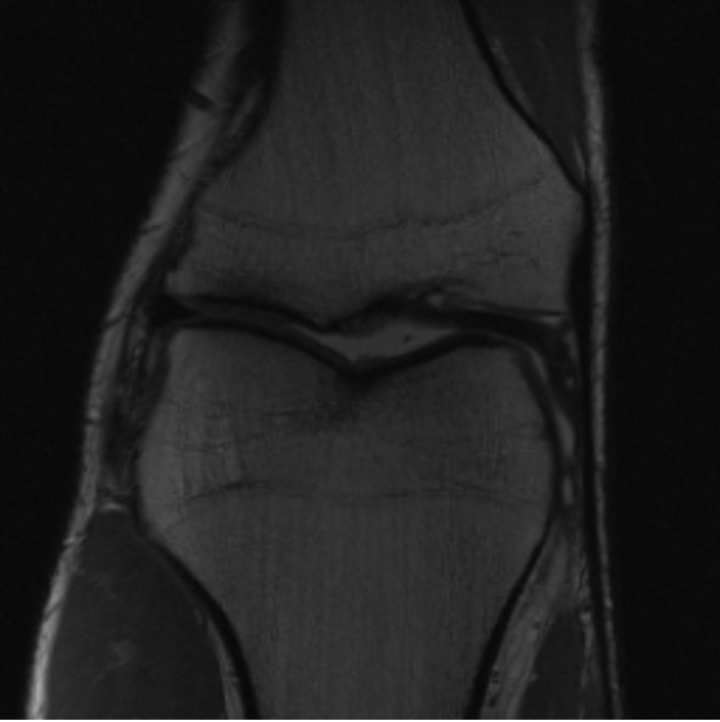

5.3 Out-of-Domain Generalisation

One way to test the generalization capability of the trained X-Diffusion is to test it on a completely different domain from an MRI dataset not seen during training. We report the single-slice results on NYU fastMRI [37, 82], a knee MRI dataset, using the X-Diffusion trained on the BRATS brain MRIs. The results are shown in Figure 9 and Table 2. It shows how successfully X-Diffusion is able to generate knee MRIs from a single image, despite not seeing knees at all in training. To qualitatively assess how realistic our generated 3D volumes were (produced from a single slice), we gave 20 generated examples alongside their real MRI counterparts to an expert orthopaedic surgeon. He was then asked to identify the real example from a given pair. The surgeon identified with certainty only 10 real knee MRIs out of 17, while could not decide on the remaining 3 of the 20 MRI pairs. This further validates the generated out-of-domain MRIs.